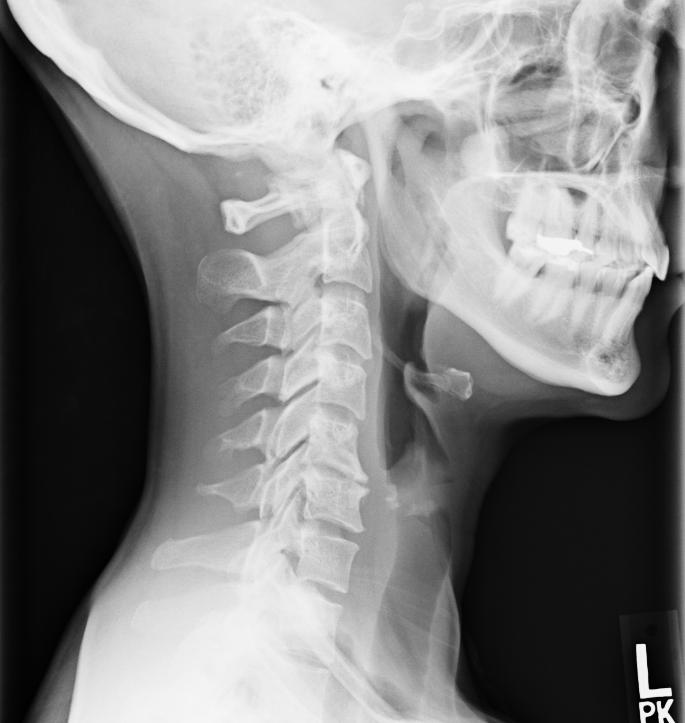

From neckinjurywakuzao.blogspot.com

Neck Injury March 2015 Most Common Radiology Misses With estimates of average diagnostic error rates ranging from 3% to 5%, there are approximately 40 million diagnostic errors involving imaging annually worldwide. In this article, we describe 10 of the most common biases (table 2) that impact radiologic decision making and provide illustrative case examples. The potential to improve diagnostic performance and reduce patient harm by identifying and learning. Most Common Radiology Misses.